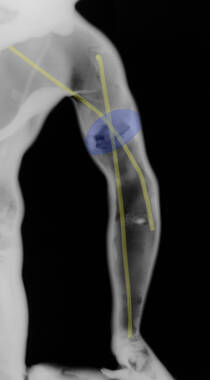

Figure 9

Figure 16

Figure 25

Figure 42

Figure 122

Figure 195